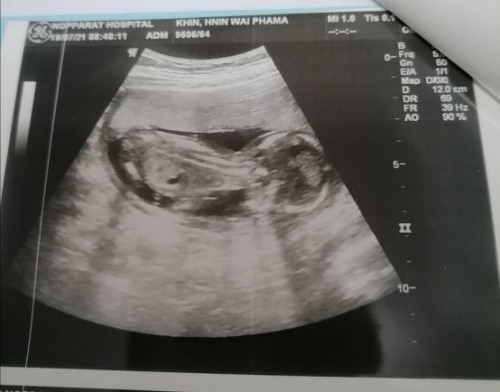

แม่! 🤰💖อวดรูปอัลตร้าซาวด์กัน

โชว์รูปแรกของเบบี้กันหน่อยน้า เพศหญิง👧หรือชาย🧑เอ่ยยย 😍🥰💜 17/09/2563

หมอบอกหนูเป็นผู้ชายคับปม

ไม่รู้เพศค่ะ ช่วยดูหน่อย